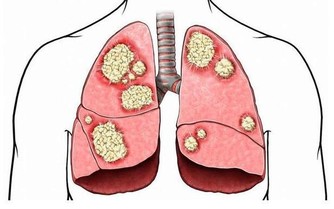

肝臟是人體代謝的重要器官,但是肝臟發病,很多時候是沒有明顯的癥狀表現的,

於是就讓很多人忽略了肝臟的疾病,

等到發現肝臟疾病的時候,通常已經很嚴重了,所以認清肝病癥狀很重要。